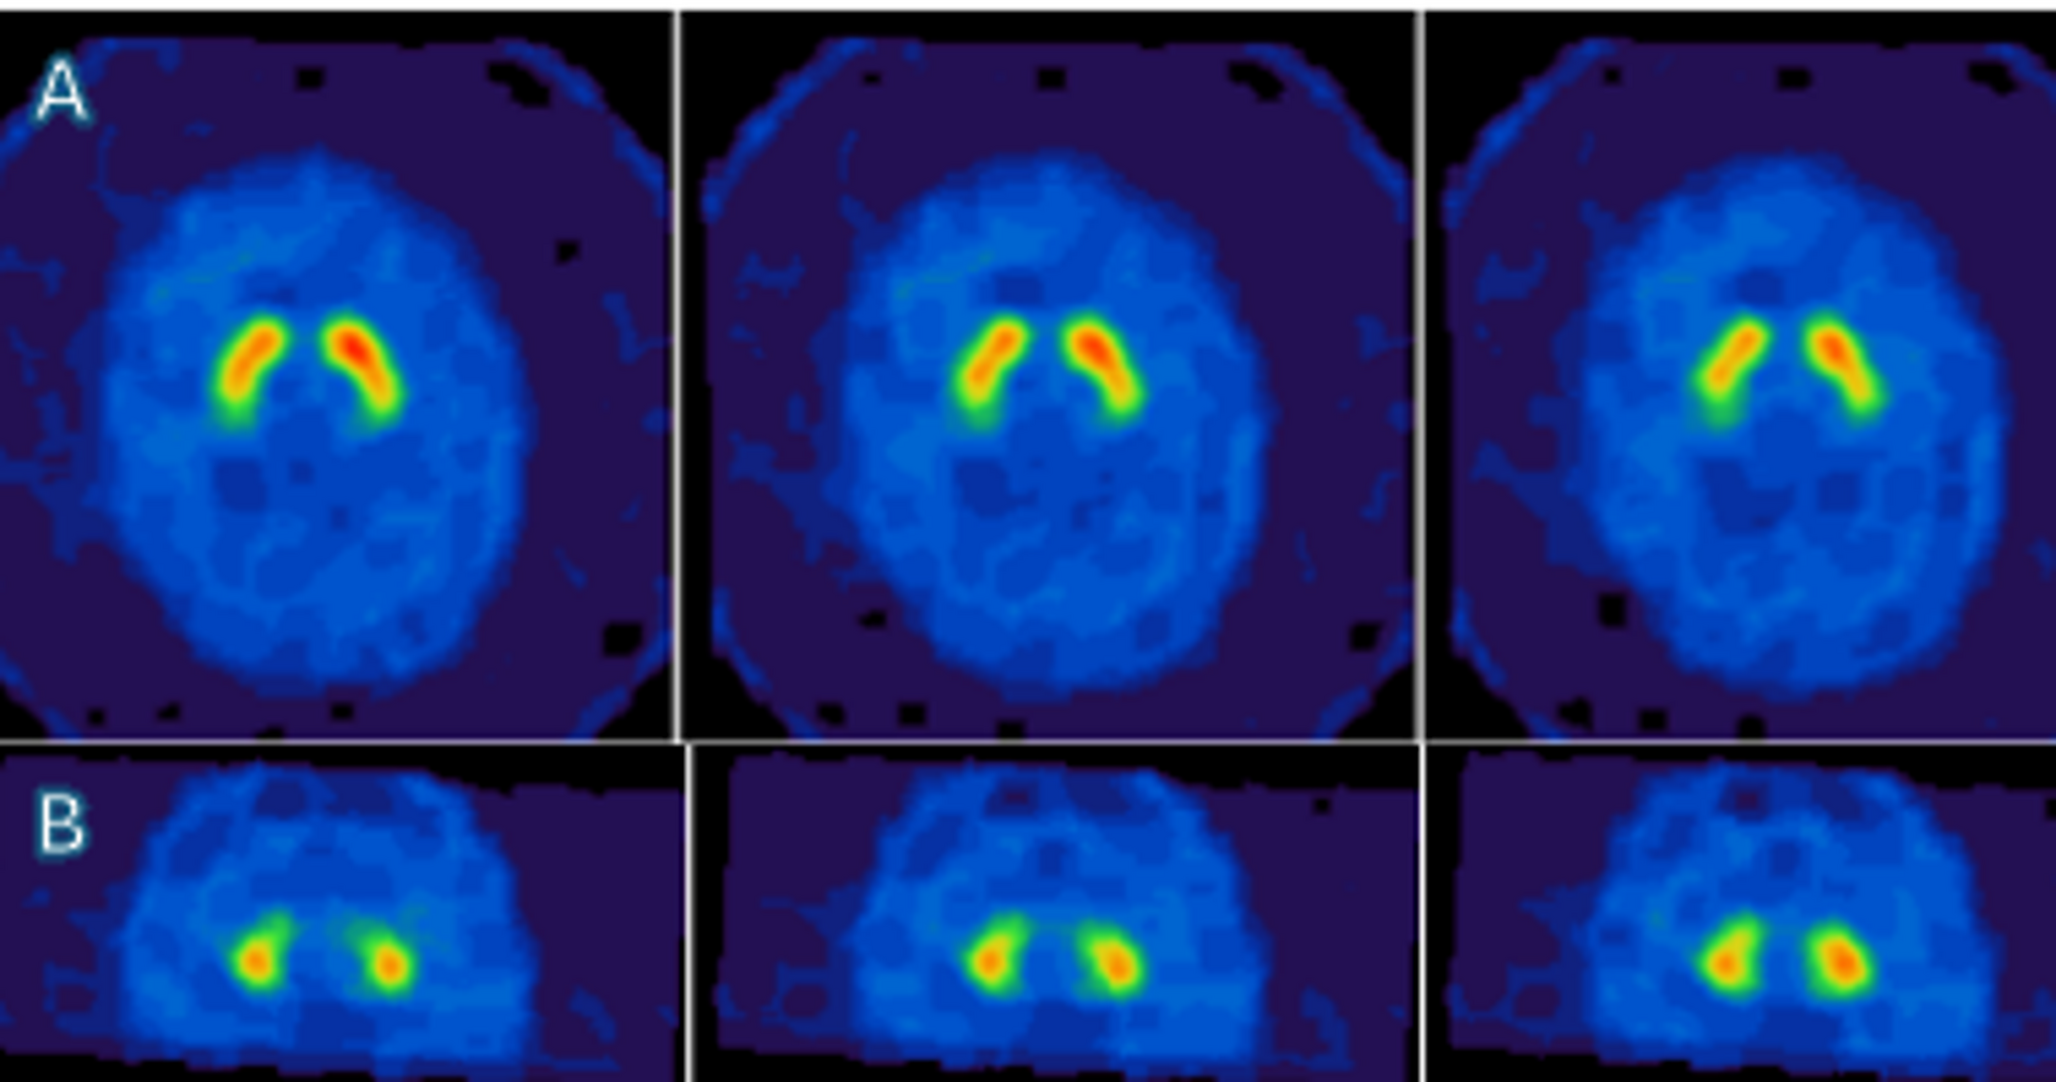

Brain magnetic resonance imaging (MRI) showed an “eye of the tiger” sign, defined by a bilateral central region with hyperintense signal surrounded by hypointensity in the globus pallidus on T2-weighted sequences (Fig. 1) [1]. There was no evidence of cerebellar or cortical atrophy. Fluorodeoxyglucose positron emission tomography (FDG-PET) and I-123 ioflupane single-photon emission computed tomography (DATscan) were normal, in accordance with previous cases reported (Fig. 2) [2, 3].

Fig. 2

The quantitative indices (specific binding ratios) of I-123 ioflupane single-photon emission computed tomography (DATscan) were considered as normal. Discriminate value reported in litterature to differenciate essential tremor/healthy subjects and parkinsonism disease are above 0.76 for putamen (Se 87%, Spe 85%) and above 1,56 for caudate nuclei (Se 82%, Spe 85%).2 (A) Axial slice shows normal uptake of dopamine in both putamen with respectively specific binding ratios at 2.1 (right putamen) and 1.65 (left putamen). (B) Coronal slice shows normal captation in both caudate nuclei with specific binding ratios at 2.08 (right caudate nucleus) and 2 (left caudate nucleus)